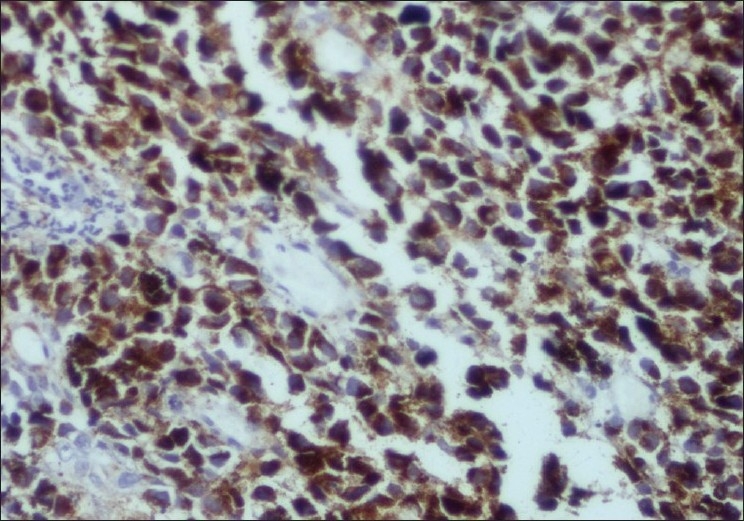

A biopsy obtained from the gastric lesion showed solid nests of large polygonal cells in the submucosa with hyperchromatic nuclei and occasional nucleoli with a deposition of a brownish black pigment within the cells suggestive of a malignant melanoma. The surrounding gastric mucosa was normal. [2]Immunohistochemistry with HMB-45 showed cytoplasmic positivity in the tumor cells. [3]

| Figure 3 Immunohistochemistry on the biopsy tissue showing cytoplasmic positivity with HMB-45.